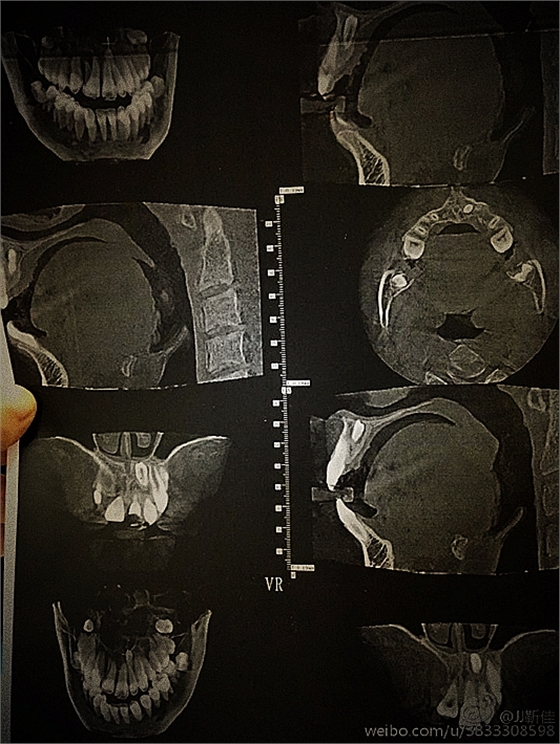

ct定位

術后拍片